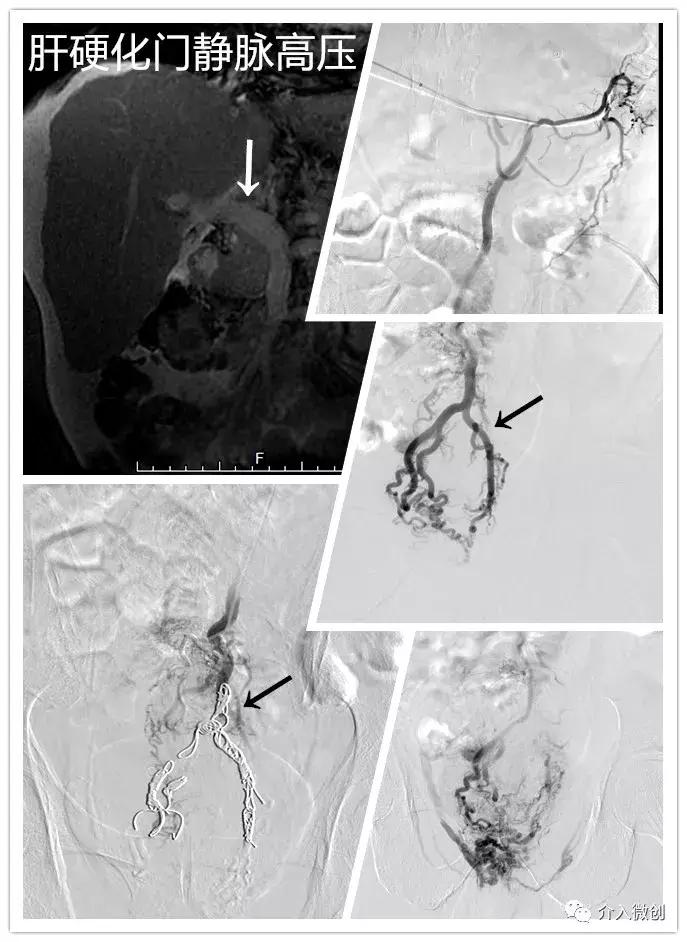

- 老年男性,肝硬化门静脉高压,既往多次出现食管胃静脉曲张破裂出血,近期反复大量便血,导致失血性休克。

- 急诊行经肝门静脉穿刺,行肠系膜下静脉造影显示直肠静脉(痔静脉)丛曲张明显,经栓塞多枚弹簧圈后血管闭塞,术后未再便血。

介入栓塞痔静脉止血